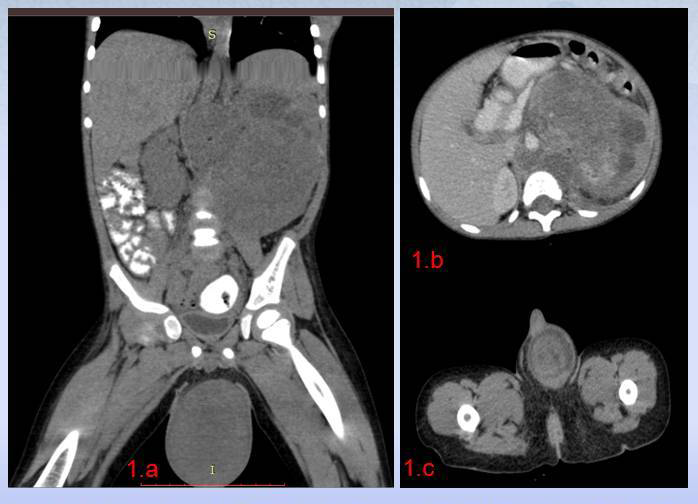

Blood biochemistory was normal except anemia. The serum Alfa Feto Protein (AFP), Humon Chorionic Gonadotropin (HCG) and Serum isoenzyme lactate dehydrogenase (LDH 1) were within normal limits. Ultrasonography suggested normal contralateral kidney and testicle. Contrast enhanced computer tomography (CECT) scan of abdomen with scrotum (shielding of right testicle) showed 16×10 cm left renal mass compressing adjacent structures, retroperitoneal lymph node enlargement, invasion of left renal vessels and inferior vena cava (below diaphragm) with a heterogenous 6×4.5 cm left testicular mass (Figure 1). Further radiology didn’t reveled any other site of metastasis.

Figure 1 1.a, b: 64 slice contrast enhanced CT scan of abdomen in coronal and axial section showing 16 ×10 cm sized heterogenous, left Renal mass, compressing adjacent structures, displacing inferior vena cava with multiple retroperitoneal lymph node enlargement and homogenous 6 ×4.5 cm sized left testicular mass; .1.c axial section of testicular mass showing homogenous testicular mass.